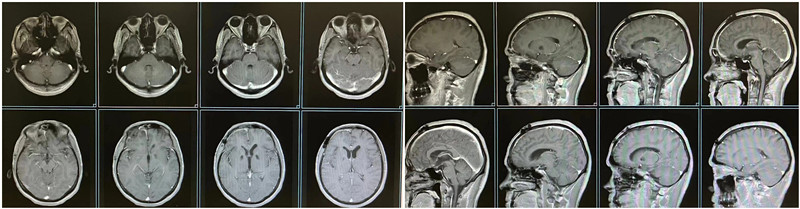

患者术后头颅MRI

手术后复查患者头颅磁共振显示:脑肿瘤完全切除。患者完全恢复正常,头痛症状完全消失,视力有所改善,四肢活动自如,能够独立行走,顺利康复出院。